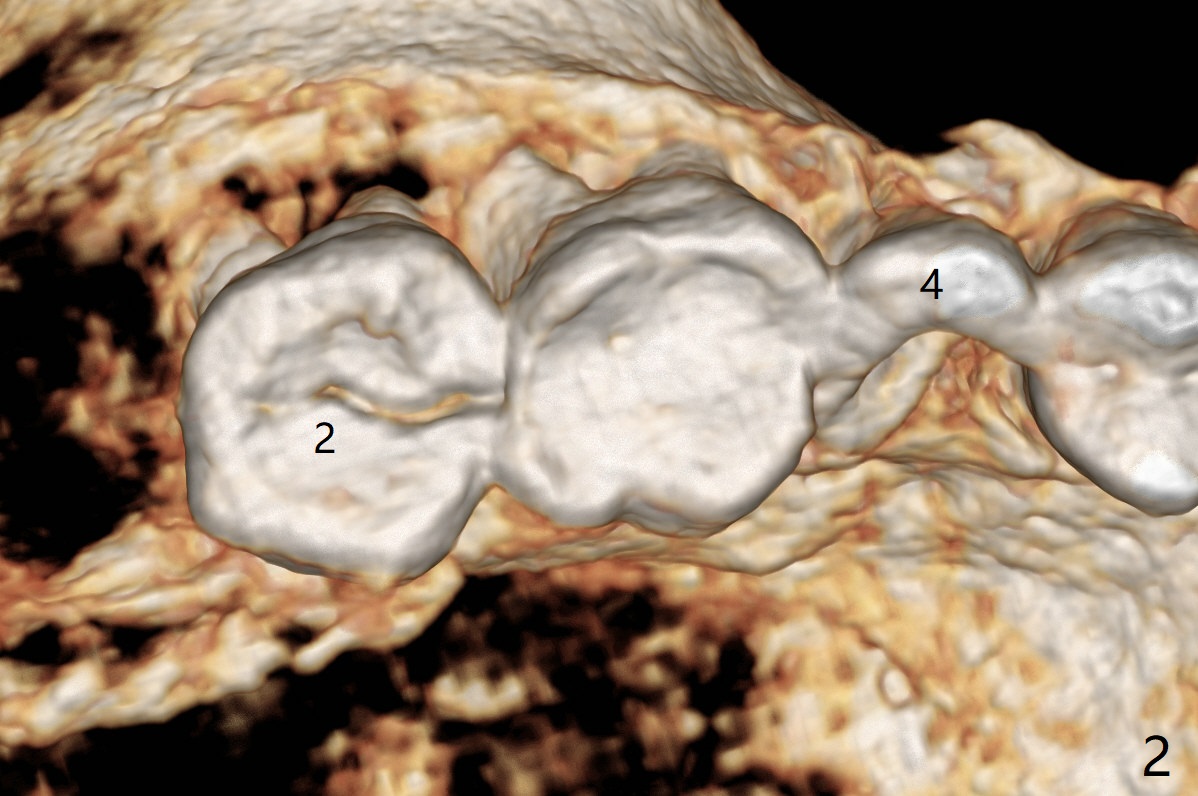

After implant placement at #13 six months post bone graft (Fig.1), reexami-nation shows that the tooth #2 cracks (Fig.2-4). The bony defect area is easier to identify with CT (between MB and P roots of #2) than without CT (M) for #13. There is no bone height reduction after extraction of #15 (Fig.5). Due to new coronal virus outbreak, the patient wants extraction first. The sinus floor perforates (*) apical to MB (Fig.6) and DB (Fig.7) roots. After debridement, sinus lift will be conducted using allograft hydrated with GEM21S liquid portion. The same mix will be used for socket preservation. With high concentration of growth factor, it is hoped that bone density in the sockets will increase quick and high enough for future implant, as compared to #13 of the same patient.